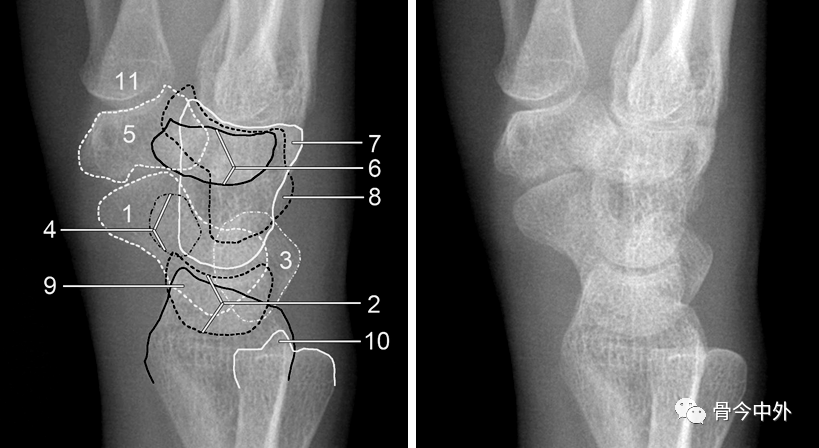

图1 成人期腕关节正侧位及舟骨蝶位片。1.舟骨;2.月骨;3.三角骨;4.豆状骨;5.大多角骨;6.小多角骨;7.头状骨;8.钩骨;9.桡骨茎突;10.尺骨茎突;11.第一掌骨基部。

图2 成人期腕关节正侧位及舟骨蝶位片。1.舟骨;2.月骨;3.三角骨;4.豆状骨;5.大多角骨;6.小多角骨;7.头状骨;8.钩骨;9.桡骨茎突;10.尺骨茎突;11.第一掌骨基部。